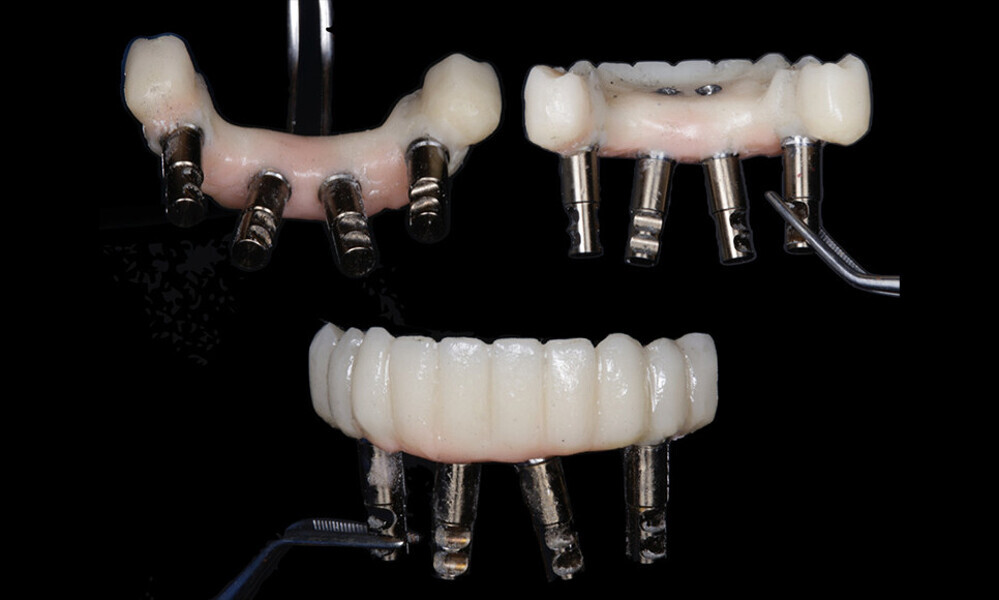

After a healing period of five months and successful osseointegration, the process for the definitive restorations was initiated. The chosen material was milled monolithic zirconia, and Variobase final abutments was used, placed on the screw-retained abutments to ensure excellent stability and retention of the definitive restorations (Figs. 69–75).

Figs. 69–75: The definitive restorations were fabricated after a five-month healing period